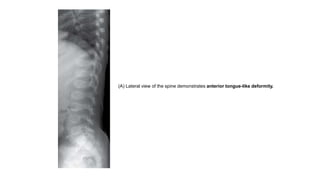

⮚ Vertebrae have a persistent oval shape in childhood with a tongue-like

protusion from the anterior aspect of vertebral bodies giving rise to

central anterior tongue appearance.

⮚ The central anterior tongue appearance is pathognomic of this entity.

⮚ However, this disappears at older age and is replaced by platyspondyly

giving rise to the short limb-short trunk dwarfism.

Pseudochondroplasia. Lateral radiograph of

spine shows typical central anterior

tongue (arrow, A) in lumbar vertebrae.

Radiograph of both hands (B) also show

multiple abnormalities of epiphyses of

metacarpals and phalanges with

secondary metaphyseal widening (arrow).

(A) Lateral view of the spine demonstrates anterior tongue-like deformity.